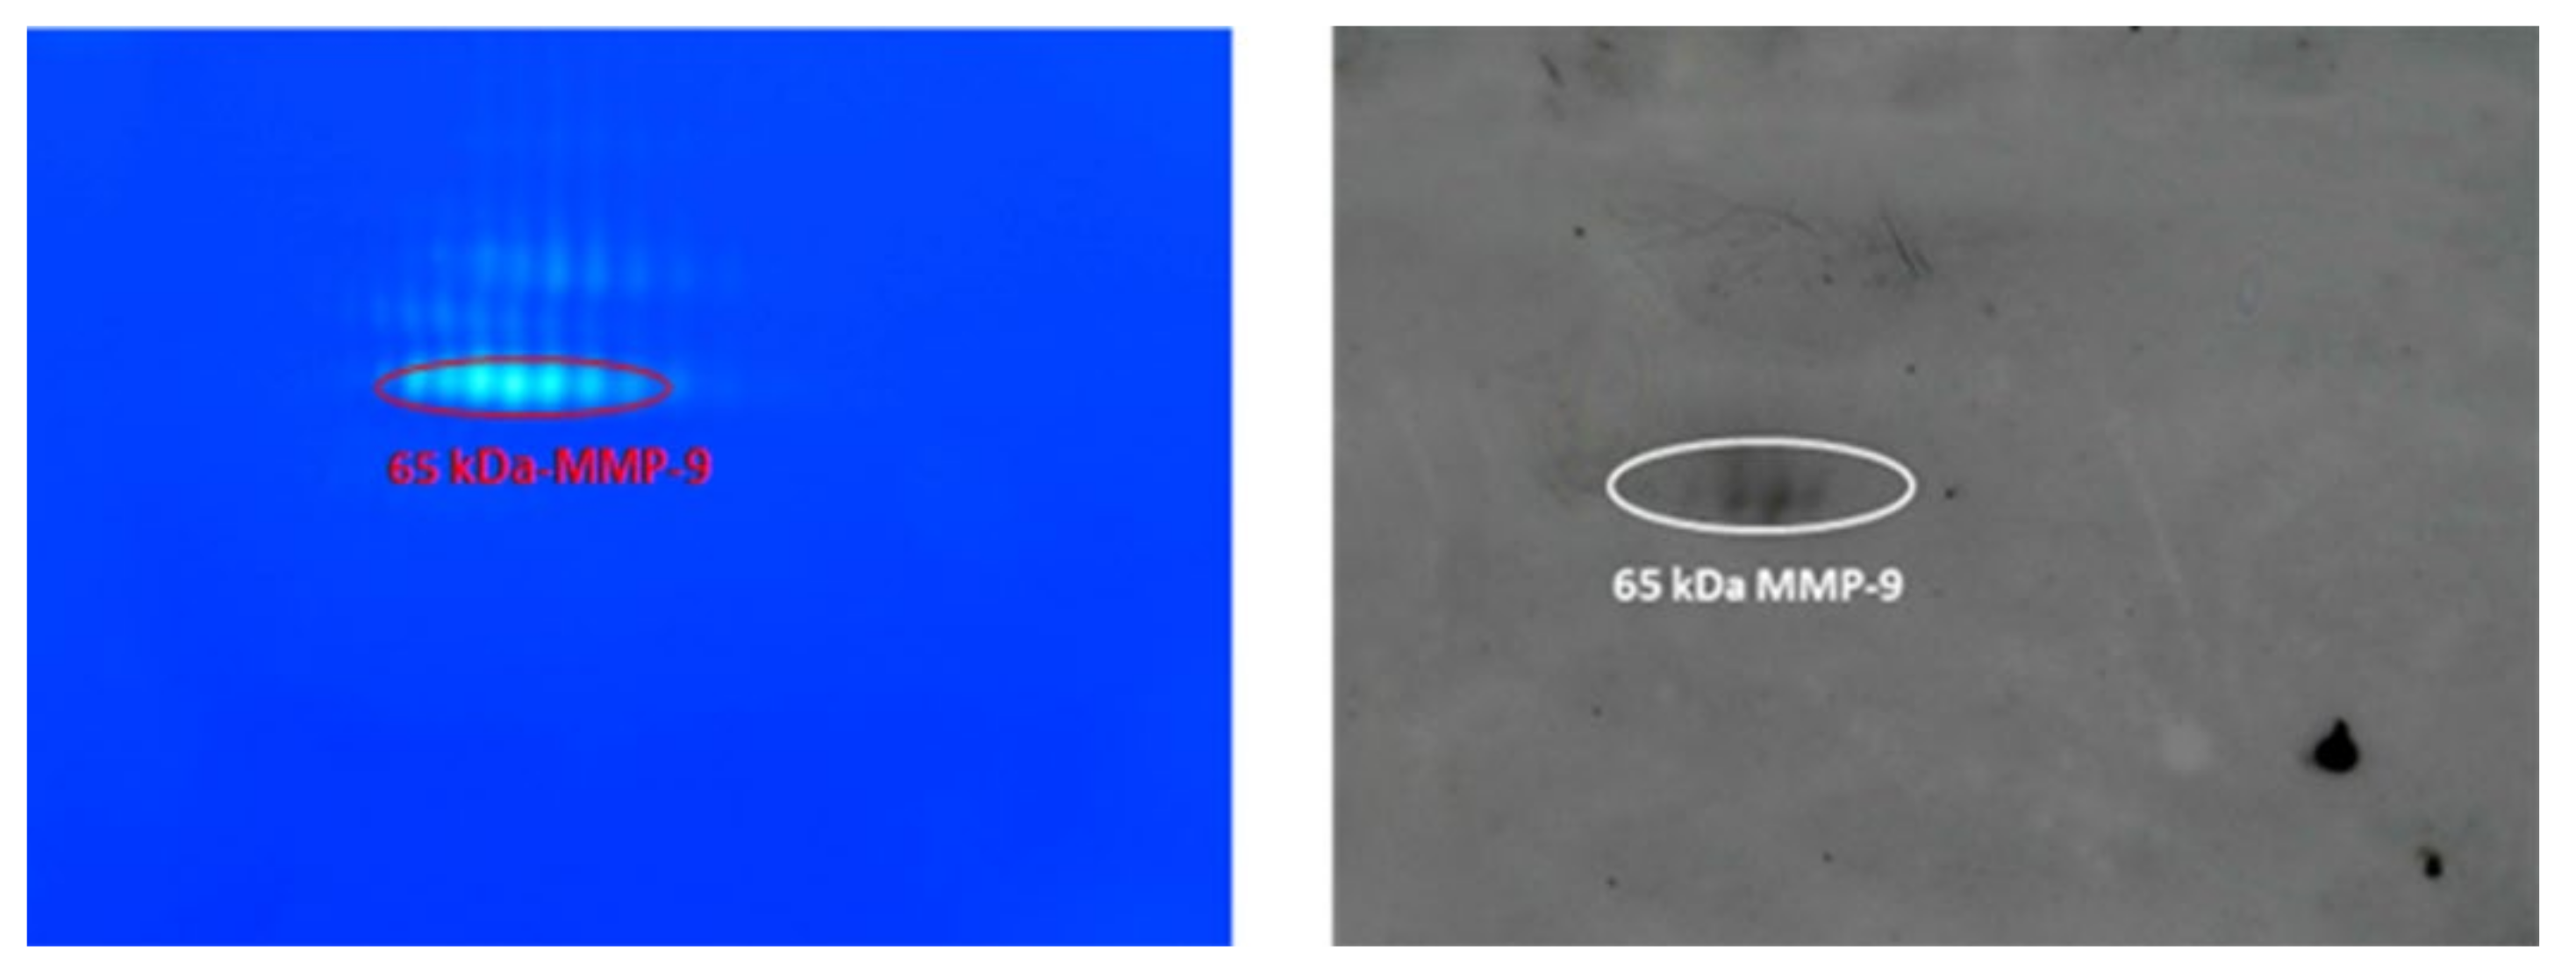

- The 65–67 kDa MMP-9 active form—a group of spots with pI range 4.6–4.9, corresponding to the marker suggested in this work.

- The fourth and last group was made of three spots at 65 kDa and pI between 5.20 and 5.35 (65-kDa MMP-9 active form).

3.4. Identification of MMP-9 and MMP-2 by Western Blot Analysis